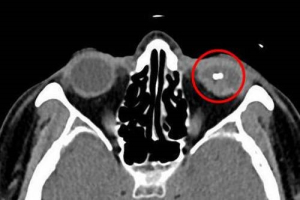

隱藏視力殺手! 眼科醫師籲使用割草機務必防護眼睛

一名五十多歲男性使用割草機除草,沒想到取下防護罩透個氣,除草機高速旋轉的刀片卻因打到草叢中石頭裂成碎片彈起,直接射入眼睛,雖緊急就醫治療,視力仍惡化至0.1以下無法恢復。花蓮慈濟醫院眼科醫師何明山指出,割草機高速旋轉動能足以使金屬或石頭瞬間碎裂飛起,若不慎打到眼睛,嚴重者可能失明,提醒使用割草機務必做好防護,即使只是想歇息片刻,先熄火再卸下裝備為上策。